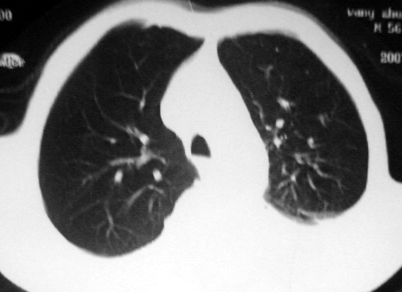

男,54岁,咳嗽,气喘半年,胸痛一月.

血性胸水

支持左肺下叶中心型肺癌(累及舌叶)伴阻塞性肺炎、膨胀不全、胸腔积液、心包少量积液。

左肺下叶中心型肺癌,伴阻塞性肺炎、左胸腔积液、心包少量积液。

1.左肺下叶中心性肺癌伴阻塞性肺炎,肺不张.

2.左侧胸腔积液,心包积液